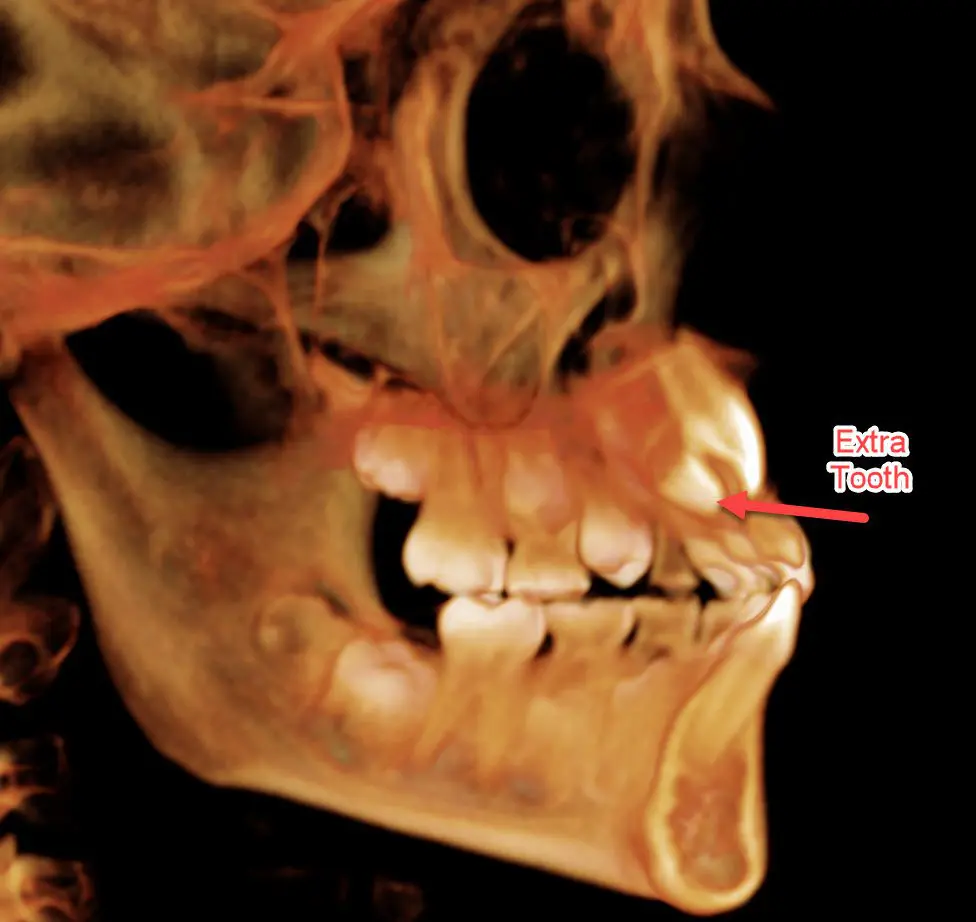

Case 3: Extra teeth. His general dentist referred this patient because his right front tooth wasn’t coming in. The 2D x-ray doesn’t look too out of the ordinary, but in the 3D view, we can see a supernumerary (extra) tooth blocking the eruption of the one we are expecting to see. We were able to refer this patient to an oral surgeon to remove the extra tooth and normalize the eruption pattern.